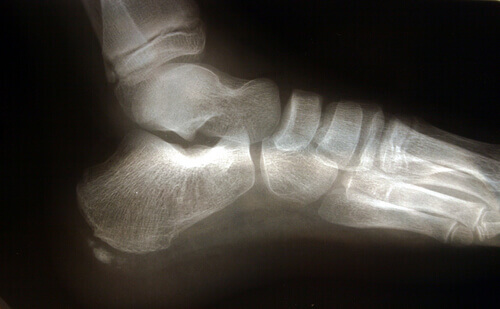

Ανατομία του ποδιού

Υπάρχουν αρκετές ανατομικές δομές που παίζουν ρόλο στην καταπόνηση της πελματιαίας περιτονίας.

Ο αχίλλειος τένοντας είναι ένας σύνδεσμος που συνδέει τους γαστροκνημίους μύες, που είναι γνωστοί ως μύες της γάμπας, και τους υποκνημιδίους μύες με το οστό της φτέρνας. Η σύσπαση του αχίλλειου τένοντα προκαλεί αύξηση της πίεσης στο οστό της φτέρνας, με αποτέλεσμα να αυξάνεται η πίεση στην πελματιαία περιτονία.

Ένας άλλος παράγοντας που πρέπει να έχουμε υπόψη αναφορικά με την ανατομία είναι ο πρηνισμός, ή με άλλα λόγια το πώς το πέλμα έρχεται σε επαφή με το έδαφος. Τα πέλματα με πλατυποδία ή με τάση υπερπρηνισμού τεντώνουν ακόμα περισσότερο την πελματιαία περιτονία, αυξάνοντας έτσι τον κίνδυνο ρήξεων λόγω της επιπλέον πίεσης που ασκείται στον ιστό.

Η πελματιαία απονευρωσίτιδα συχνά συνδέεται με την ύπαρξη άκανθας πτέρνας, αν και δεν αποτελεί καθοριστικό παράγοντα.